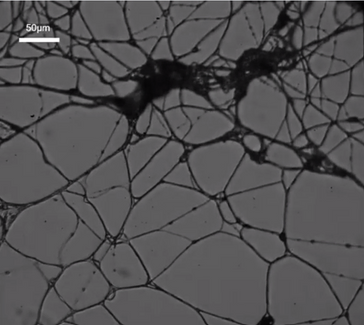

Scientists have long been on a quest to find a way to implant electrodes that interface with neurons into the human brain. If successful, the idea could have huge implications for the treatment of Parkinson’s disease and other neurological disorders. A team of researchers from Italy and the UK, by showing that the world’s favorite wonder-material, graphene, can successfully interface with neurons!

Previous efforts by other groups using treated graphene had created an interface with a very low signal to noise ratio. But an interdisciplinary collaborative effort by the University of Trieste and the Cambridge Graphene Centre has developed a significantly improved electrode by working with untreated graphene.

“For the first time we interfaced graphene to neurons directly,” said Professor Laura Ballerini of the University of Trieste in Italy. “We then tested the ability of neurons to generate electrical signals known to represent brain activities, and found that the neurons retained their neuronal signaling properties unaltered. This is the first functional study of neuronal synaptic activity using uncoated graphene based materials.”

Prior to experimenting with graphene-based substrates (GBS), scientists implanted microelectrodes based on tungsten and silicon. Proof-of-concept experiments were successful, but these materials seem to suffer from the same fatal flaws. The body’s reaction to the insertion trauma is to form scarring tissue, inhibiting clear electrical signals. The structures were also prone to disconnecting, due to the stiffness of the materials, which were unsuitable for a semi-fluid organic environment.